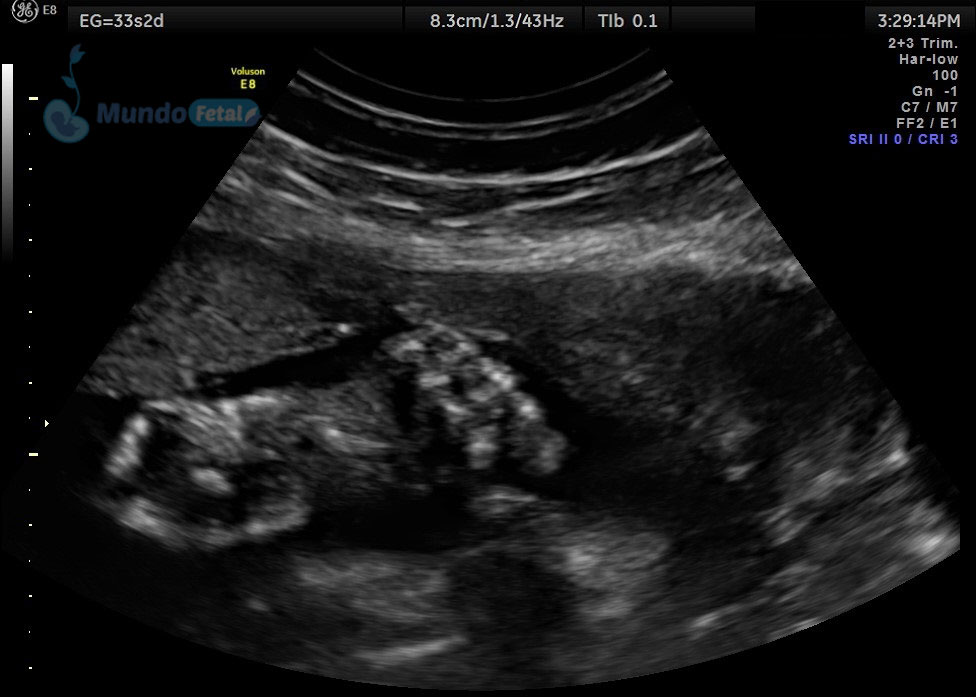

Ultrasonido 2do Trimestre 18-23 Semanas (Estructural o Anatómico)

Entre las 18 y 22 semanas, el feto ha desarrollado la mayoría de sus estructuras anatómicas, permitiéndonos valorar de manera detallada todos los órganos del bebe, descartando anomalías anatómicas fetales y datos de cromosomopatías. Prediciendo además preeclampsia (Doppler de arterias uterinas) y parto prematuro (por medio de la medición de la longitud del cérvix). En manos expertas, la detección de anomalías anatómicas supera el 80%.